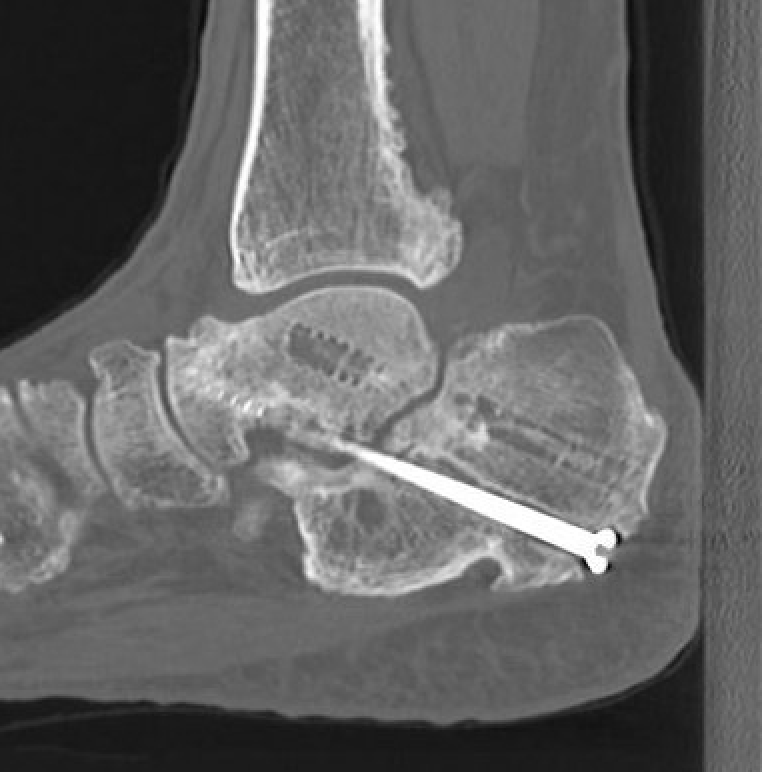

CT

Subluxation of TNJ with advanced STJ OA

TNJ OA with posterior / medial / anterior facet OA of the subtalar joint

Fixation

- 6.5 mm/ 8.0 mm cannulated screw

- inferior calcaneum into body and neck of talus / talus to calcaneum